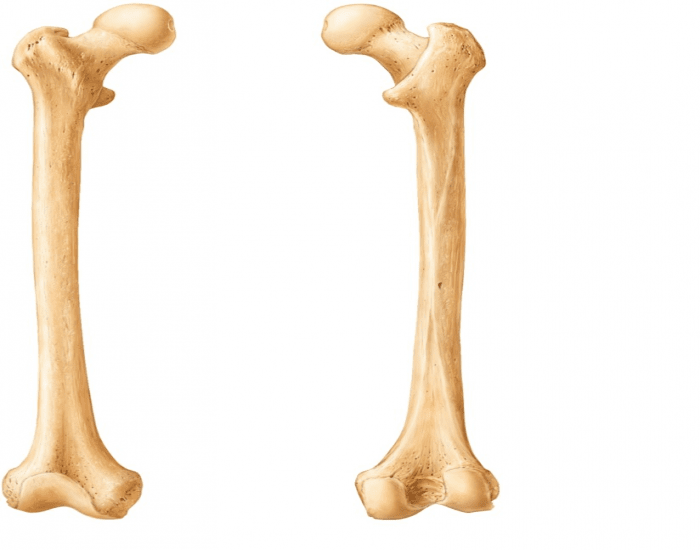

Анатомия фибулы: Подробные фотографии и схемы